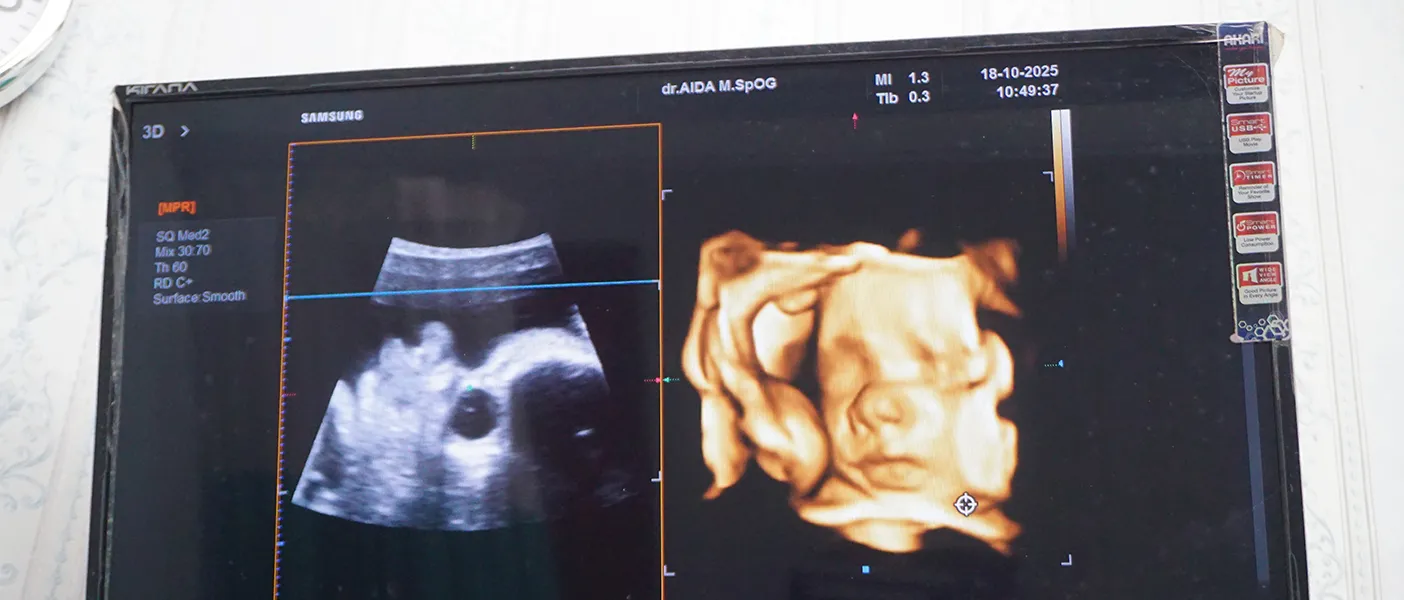

USG dengan Teknologi Canggih

Pelayanan USG lengkap bersama Dokter Spesialis Radiologi serta Dokter Spesialis Obgyn khusus kandungan

USG 4 Dimensi

USG 4D di Rumah Sakit Galeri Candra memudahkan orang tua melihat janin dengan lebih jelas dan detail.